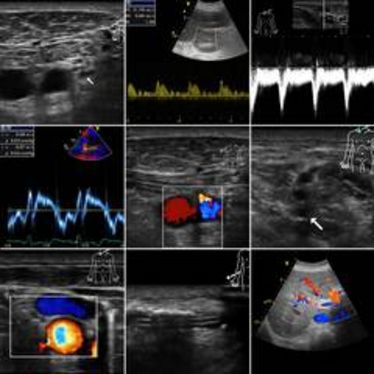

2. Münsteraner Ultraschall-Kurs

2. Münsteraner Ultraschall-Kurs

2. Münsteraner Ultraschall-Kurs

2. Münsteraner Ultraschall-Kurs

International Summer School of Ultrasound

International Summer School of Ultrasound

Sonographie-Aufbaukurs: Weiterführende Differentialdiagnostik des Feten

Sonographie-Aufbaukurs: Weiterführende Differentialdiagnostik des Feten

Doppler-Sonographie Schwangerschaftsdiagnostik - Interdisziplinärer Grundkurs

Doppler-Sonographie Schwangerschaftsdiagnostik - Interdisziplinärer Grundkurs